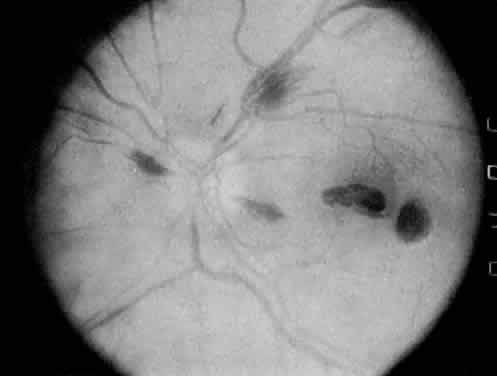

The most common ocular manifestations of TTP include papilledema, extraocular muscle palsies, and visual field defects, which usually are secondary to concomitant CNS involvement.75 Retinal findings consist of hemorrhages, retinal vascular occlusions, and serous detachments76,77 (Figs. 8 to 10). The cause of the serous detachments appears to be focal occlusion of the choriocapillaris resulting in retinal pigment epithelial damage and blood-retinal barrier disruption.76,77 Findings on fluorescein angiography are characterized by focal areas of nonperfusion of the choriocapillaris associated with late leakage into the subretinal space76 (Fig. 11). This is consistent with histopathologic studies that show occlusion of the choriocapillaris and large choroidal vessels, presumably by fibrin, with overlying necrosis of thepigment epithelium.75,76 TTP also has been linked in one case report with Purtscher retinopathy.78

Fig. 10. A 42-year-old woman with thrombotic thrombocytopenic purpura and neurosensory retinal detachments. (Courtesy of Jerry Neuwirth, MD.)

Fig. 11. Fluorescein angiogram of patient with thrombotic thrombocyto-penic purpura showing late choroidalhyperfluorescence caused by focal areas of choriocapillaris nonperfusion. (Courtesy of Jerry Neuwirth, MD.)

Clinically, the development of serous retinal detachments usually is associated with exacerbations of TTP and the development of acute hypertension. Although serous retinal detachments have been described as a preterminal event, resolution of the detachments with subsequent pigment epithelial changes may occur when the underlying hypertension and thrombocytopenia are controlled.77